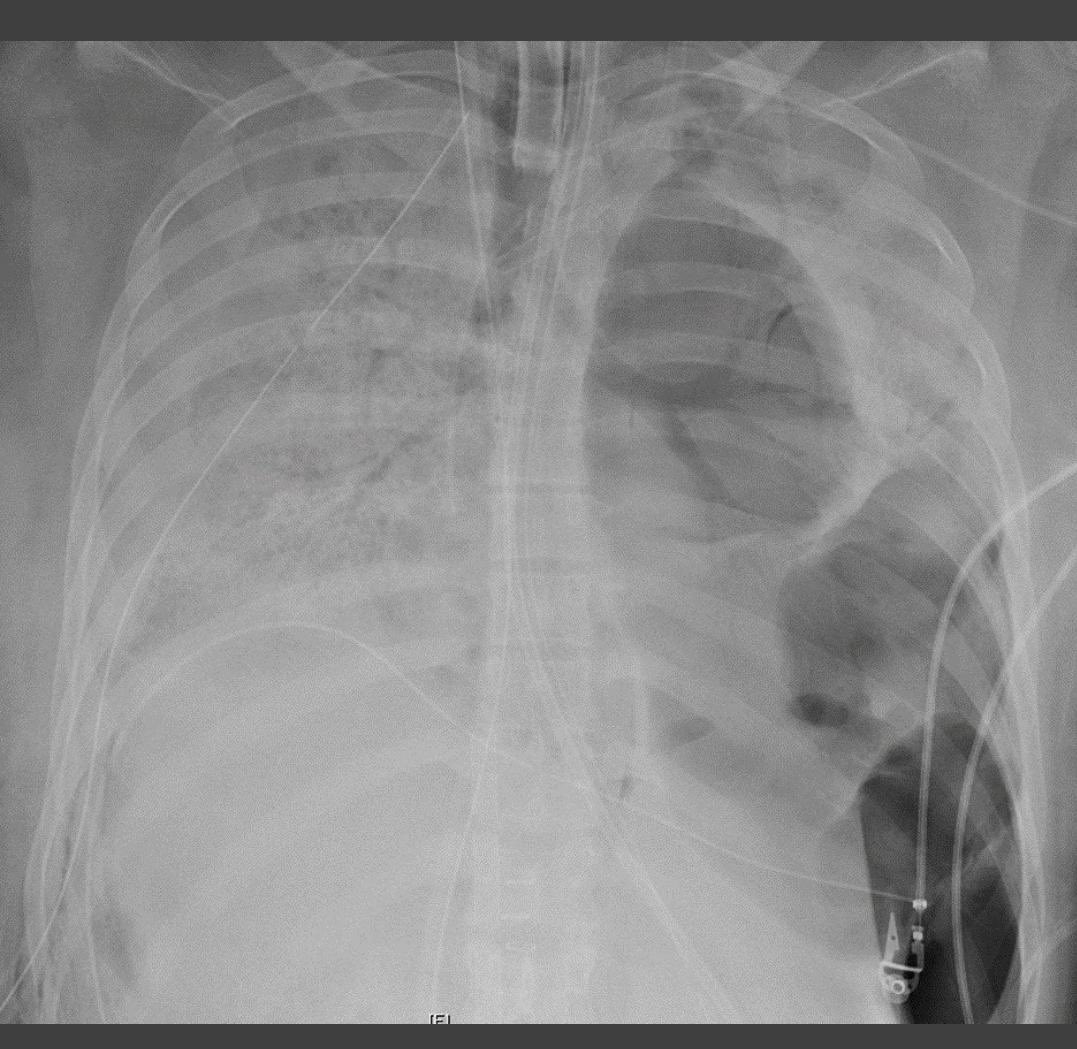

٤-هذه صورة للرئة الطبيعية قبل الالتهاب وصورة بعد دخول الرئة في متلازمة الضائقة التنفسية الحادة ARDS (هذا البياض الشديد عبارة عن التهاب حاد) ويصعب تبادل الغازات التنفسية وتصبح متصلبة ولاتستطيع العمل ومن ثم يتم وضع المريض علىً جهاز تنفسي ..